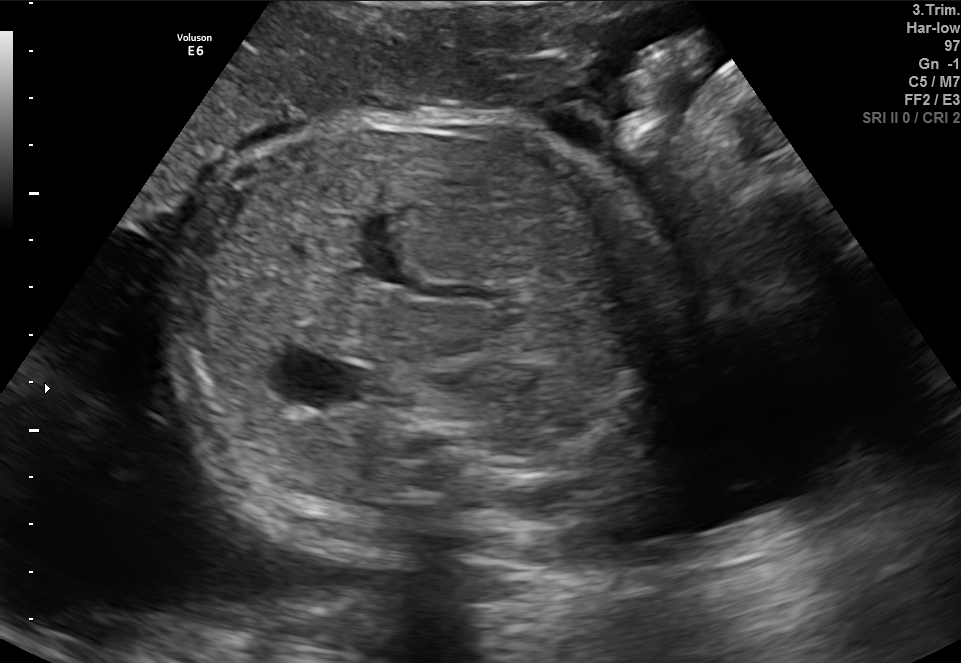

Refer to caption

(a) Fetal abdomen

(b) Fetal brain

(c) Fetal femur

(d) Fetal thorax

(e) Maternal cervix

(f) Other

Figure 2: Examples of synthetic images generated by the trained diffusion model.

5.1 Visualization of Synthetic Images

The generated images were visually assessed by examining a sample of synthetic images from each of the six classes. The synthetic images were compared with the real images from the FETAL_PLANES_DB dataset in Figure 1 to evaluate their realism and similarity. Example images from the diffusion model are shown in Figure 2, where we observe that the synthetic images closely resemble the real images in terms of texture, structure, and class-specific features. This addition emphasizes the visual quality of the generated images, which was a key aspect of evaluating the success of diffusion models in this context.